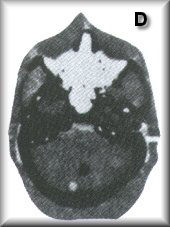

D部分:擬人部分在空氣對比的內耳和骨折的巖骨中提供實際的聽覺小骨。后顱窩小腫瘤被放置在大多數掃描儀難以成像的區域。

RS-250 D部分